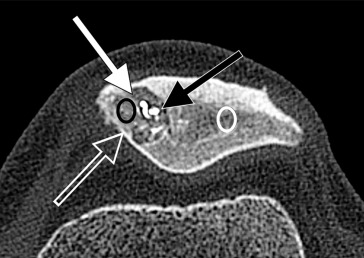

"Dorsal Defect of The Patella: an Efficient, Safe, and Minimally Invasive Treatment with Percutaneou Sclerotherapy Using Radiopaque Gelified Ethanol" sciencedirect.com/science/articl… Sylvain Grange CHU de Saint-Étienne JVIR

Dorsal Defect of the Patella: An Efficient, Safe, and Minimally Invasive Treatment with Percutaneous Sclerotherapy Using Radiopaque Gelified Ethanol ow.ly/o1iC50HL1Ea #irad